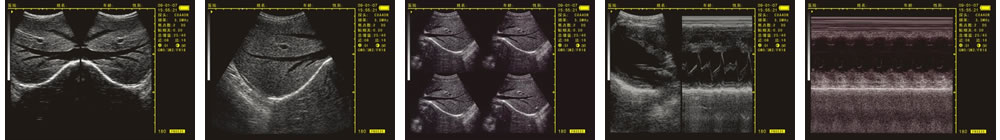

優質的成像效果